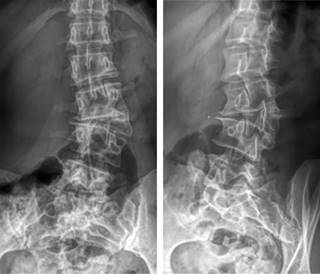

Radiografías de la columna vertebral. Radiología de la escoliosis. Una radiografía de la columna lumbosacra es una imagen de los pequeños huesos vértebras en la parte baja de la columna.

Debe tener presente que la escoliosis o la alteración en la normalidad de la columna respecto a su trayecto la mayoría de las veces no requiere de operación pero si puede necesitar algunos ejercicios físicos que ayudan a a mejorar las molestias producidas. Radiología de la escoliosis. Departamentos de Radiología y Pediatría Facultad de Medicina Pontificia Universidad Católica de Chile. Radiografia de columna vertebral desviada. PDF On Jan 1 2009 Julio Duart and others published Radiología de la columna vertebral Find read and cite all the research you need on ResearchGate. La radiografía es la técnica primaria y principal en el estudio de los trastornos de la alineación de la columna vertebral esto es debido tanto a la claridad y gran utilidad diagnóstica de las imágenes que proporciona como al fácil acceso y rapidez de la exploración. Se trata del nombre más técnico para referirnos a una espalda torcidaEn Clínicas H3 disponemos de los mejores profesionales que estudiarán tu caso de escoliosis o columna desviada y realizarán el diagnóstico más apropiado. La escoliosis ocurre cuando las vértebras de la columna torácica se encuentran desviadas lateralmente giradas formando una C o una S lo que puede afectar la cervical dorsal yo lumbar. Debe tener presente que la escoliosis o la alteración en la normalidad de la columna respecto a su trayecto la mayoría de las veces no requiere de operación pero si puede necesitar algunos ejercicios físicos que ayudan a a mejorar las molestias producidas.